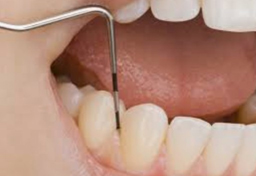

実際の治療としては、まず歯面のプラークおよび歯石の付着状況・歯周ポケットの深さ・歯肉からの出血の有無・歯の動揺度を検査、測定し、歯肉炎および歯周炎に罹患しているかどうかを確認します。

検査にて歯肉炎・歯周炎と診断された場合は、スケーラーと呼ばれる専門の器具を用いて、プラークおよび歯石除去を行います。状態によっては痛みを伴う場合がありますので、必要に応じて麻酔を行う場合があります。